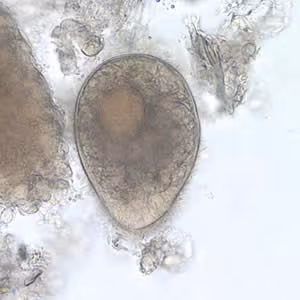

Balantidium coli cysts in wet mounts.

Both Balantidium coli trophozoites and cysts may be shed in stools. Both stages may occur in diarrheal stools, and usually only cysts are observed formed stools. Trophozoites are characterized by: their large size (40 µm to 200 µm), the presence of cilia on the cell surface, a cytostome, and a bean shaped macronucleus which is often visible and a smaller, less conspicuous micronucleus. Cysts are seen less frequently and range in size from 50 µm to 70 µm. B. coli trophozoites can also invade tissue.